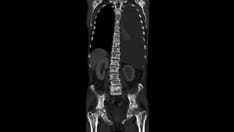

Escherichia coli right pyelonephritis.